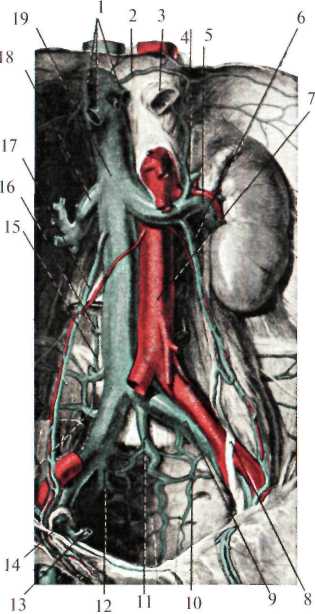

Сосуды и нервы забрюшинного пространства

В клетчатке забрюшинного пространства спереди и с боков тел поясничных позвонков расположены: брюшная аорта, нижняя полая вена, восходящие поясничные вены, поясничная часть симпатического ствола и лимфатический проток.

Брюшная аорта (aorta abdominalis) на уровне XII грудного позвонка, пройдя через аортальное отверстие диафрагмы (hiatus aorticus diaphragmatis), вступает в забрюшинное пространство, располагаясь несколько левее от средней линии, и на уровне IV поясничного позвонка делится на правую и левую общие подвздошные артерии (рис.2.8). Кпереди от аорты лежит поджелудочная железа, восходящая часть 12-перстной кишки и корень брыжейки тонкой кишки, справа – нижняя полая вена, слева – поясничная часть левого симпатического ствола.

От брюшного отдела аорты отходят парные и непарные ветви. Последние берут начало от передней поверхности аорты. К ним относятся: чревный ствол (truncus coeliacus), отходящий от аорты на уровне XII грудного позвонка, верхняя брыжеечная артерия (a. mesenterica superior) – I поясничного позвонка, нижняя брыжеечная артерия (a. mesenterica inferior) – III-IV поясничных позвонков, а также может быть средняя крестцовая артерия (a.sacralis mediana).

Парные ветви отходят от боковых стенок аорты: нижние диафрагмальные артерии (aa. phrenicae inferiores), средние надпочечниковые артерии (aa. suprarenales mediae), почечные артерии (aa. renales), яичковая или яичниковая артерии (a. testiculariss, s. ovarica), 4-е пары поясничных артерий (aa. lumbales).

Нижняя полая вена (v. cava inferior) образуется за счет слияния общих подвздошных вен (vv. iliacae communes) на уровне IV-V поясничных позвонков, располагается справа от брюшной аорты и через foramen v.cavae проникает в грудную полость (рис.2.9). Снаружи от нее лежит поясничная часть мочеточника. Спереди, на уровне III поясничного позвонка, вену пересекает корень брыжейки тонкой кишки и восходящая часть 12-перстной кишки. Позади нижней полой вены лежит правый симпатический ствол, поясничные артерии и вены (truncus sympaticus dexter, aa. et vv. lumbales) и правая ножка поясничной ножки диафрагмы.

В нижнюю полую вену впадают главным образом парные ветви: нижние диафрагмальные (vv. phrenicae inferiores), средние надпочечниковые (vv. suprarenales mediae), почечные (vv. renales), правая яичковая (v. testicularis dextra), левая яичковая вена (v. testicularis sinistra, впадает в левую почечную вену), четыре поясничные вены, а также печеночные вены, несущие очищенную печенью кровь. Непарные ветви (v. coeliaca, v. mesenterica superior et v. mesenterica inferior) впадают в воротную вену.

От четырех поясничных вен, впадающих в нижнюю полую вену, отходят восходящие поясничные вены (vv. lumbales ascendens), которые проходя между внутренними и средними ножками диафрагмы, образуют справа непарную вену (v. azygos) и слева полунепарную вену ( v. hemiazygos). В заднем средостении непарная и полунепарная вены располагаются по переднебоковой поверхности позвоночника, на уровне VII-VIII грудных позвонков полунепарная вена впадает в непарную, а непарная вена, перекидываясь через корень правого легкого, – в верхнюю полую вену. Непарная и полунепарная вены с практической точки зрения играют большую роль в образовании заднего кава-кавального анастомоза (рис.2.10).

Нервы забрюшинного пространства представлены поясничным отделом симпатического ствола, симпатическими сплетениями и ветвями блуждающих нервов.

Поясничный отдел симпатического ствола (pars lumbalis truncus sympathicus).

Проходит между латеральными и промежуточными ножками диафрагмы и ложится на переднюю поверхность тел поясничных позвонков.

Симпатический ствол состоит из 4-5 узлов и волокон, связывающих эти узлы. Кроме того, каждый из стволов посредством соединительных ветвей (rr. communicantes) связан со спинномозговыми нервами. Между правым и левым симпатическими стволами имеются соединительные ветви.

Чревное сплетение (plexus coeliacus) формируется вокруг основания чревного ствола, примыкая к внутренним краям обоих надпочечников. Оно образовано двумя чревными узлами (gangll. coeliaca), чаще полулунной формы, к которым подходит большой и малый внутренностные нервы, ветви обоих блуждающих нервов, грудного аортального сплетения, а также от правого диафрагмального нерва.

Нервы, отходящие от чревного сплетения, участвуют в образовании целого ряда других сплетений (надпочечникового, почечного, верхнего и нижнего брыжеечного, аорто-абдоминального), иннервирующих органы брюшной полости и забрюшинного пространства.

Лимфатическая система забрюшинного пространства представлена богатой сетью лимфатических сосудов и узлов. Множественные лимфатические сосуды, собирающие лимфу от нижних конечностей, органов таза, брюшной полости, забрюшинного пространства, а также от стенок живота в конечном счете образуют три ствола: два парных поясничных (trunci lumbales) и непарный кишечный (truncus intestinalis). На уровне I поясничного и XII грудного позвонков эти стволы сливаются и образуют так называемую цистерну грудного протока (cysterna chili), продолжением которой служит грудной проток (ductus thoracicus). Последний проходит между медиальными ножками диафрагмы вместе с брюшной аортой, располагаясь справа от нее, и впадает в левый венозный угол, образованный внутренней яремной и подключичной венами. Вокруг аорты на всем ее протяжении залегают регионарные лимфатические узлы.